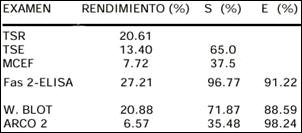

La búsqueda de huevos en heces es poco sensible, no aparecen en la fase aguda, en la fase crónica se deben repetir varias veces por la intermitencia en la eliminación de huevos. Los falso positivos se reportan cuando se ingieren hígado de animales infestados (3). A veces en ausencia de huevos en heces se puede encontrarlos en el jugo duodenal. Los métodos tienen diferentes rendimientos, como los mostrados en la tabla 3, en la que se aprecia que la Técnica de Sedimentación Rápida modificada por Lumbreras (TSR) tiene mayor rendimiento que la Técnica de Sedimentación Espontánea (TSE) y el Método de Concentración Eter-Formol (MCEF), tal vez porque en el primer método se utiliza mayor cantidad de muestra (4-8gr) que en los dos restantes (1-2 gr). La Técnica de Kato Katz ha sido empleada en el diagnóstico de la infestación experimental por Fasciola hepática, siendo limitada su aplicación clínica por su baja sensibilidad (14-17).

Las técnicas inmunológicas tienen la ventaja de ser aplicables durante todas las fases de la enfermedad, especialmente en la fase aguda y en las formas extrahepáticas. De ellas el Fas2-ELISA y el Arco 2 ofrecen una alta sensibilidad y especificidad respectivamente, habiendo sido validadas para el diagnóstico de las fases aguda y crónica, aunque en la serie de Hammami la detección de antígenos de 57 y 29 kDa por la Técnica deWestern blot alcanzan una especificidad de 100% y sensibilidades de 79 y 93% (18-20). Algunos de estos métodos puede dar reacción cruzada con equinococosis y paragonimiosis (4,10).

Tabla 3. Métodos de diagnóstico